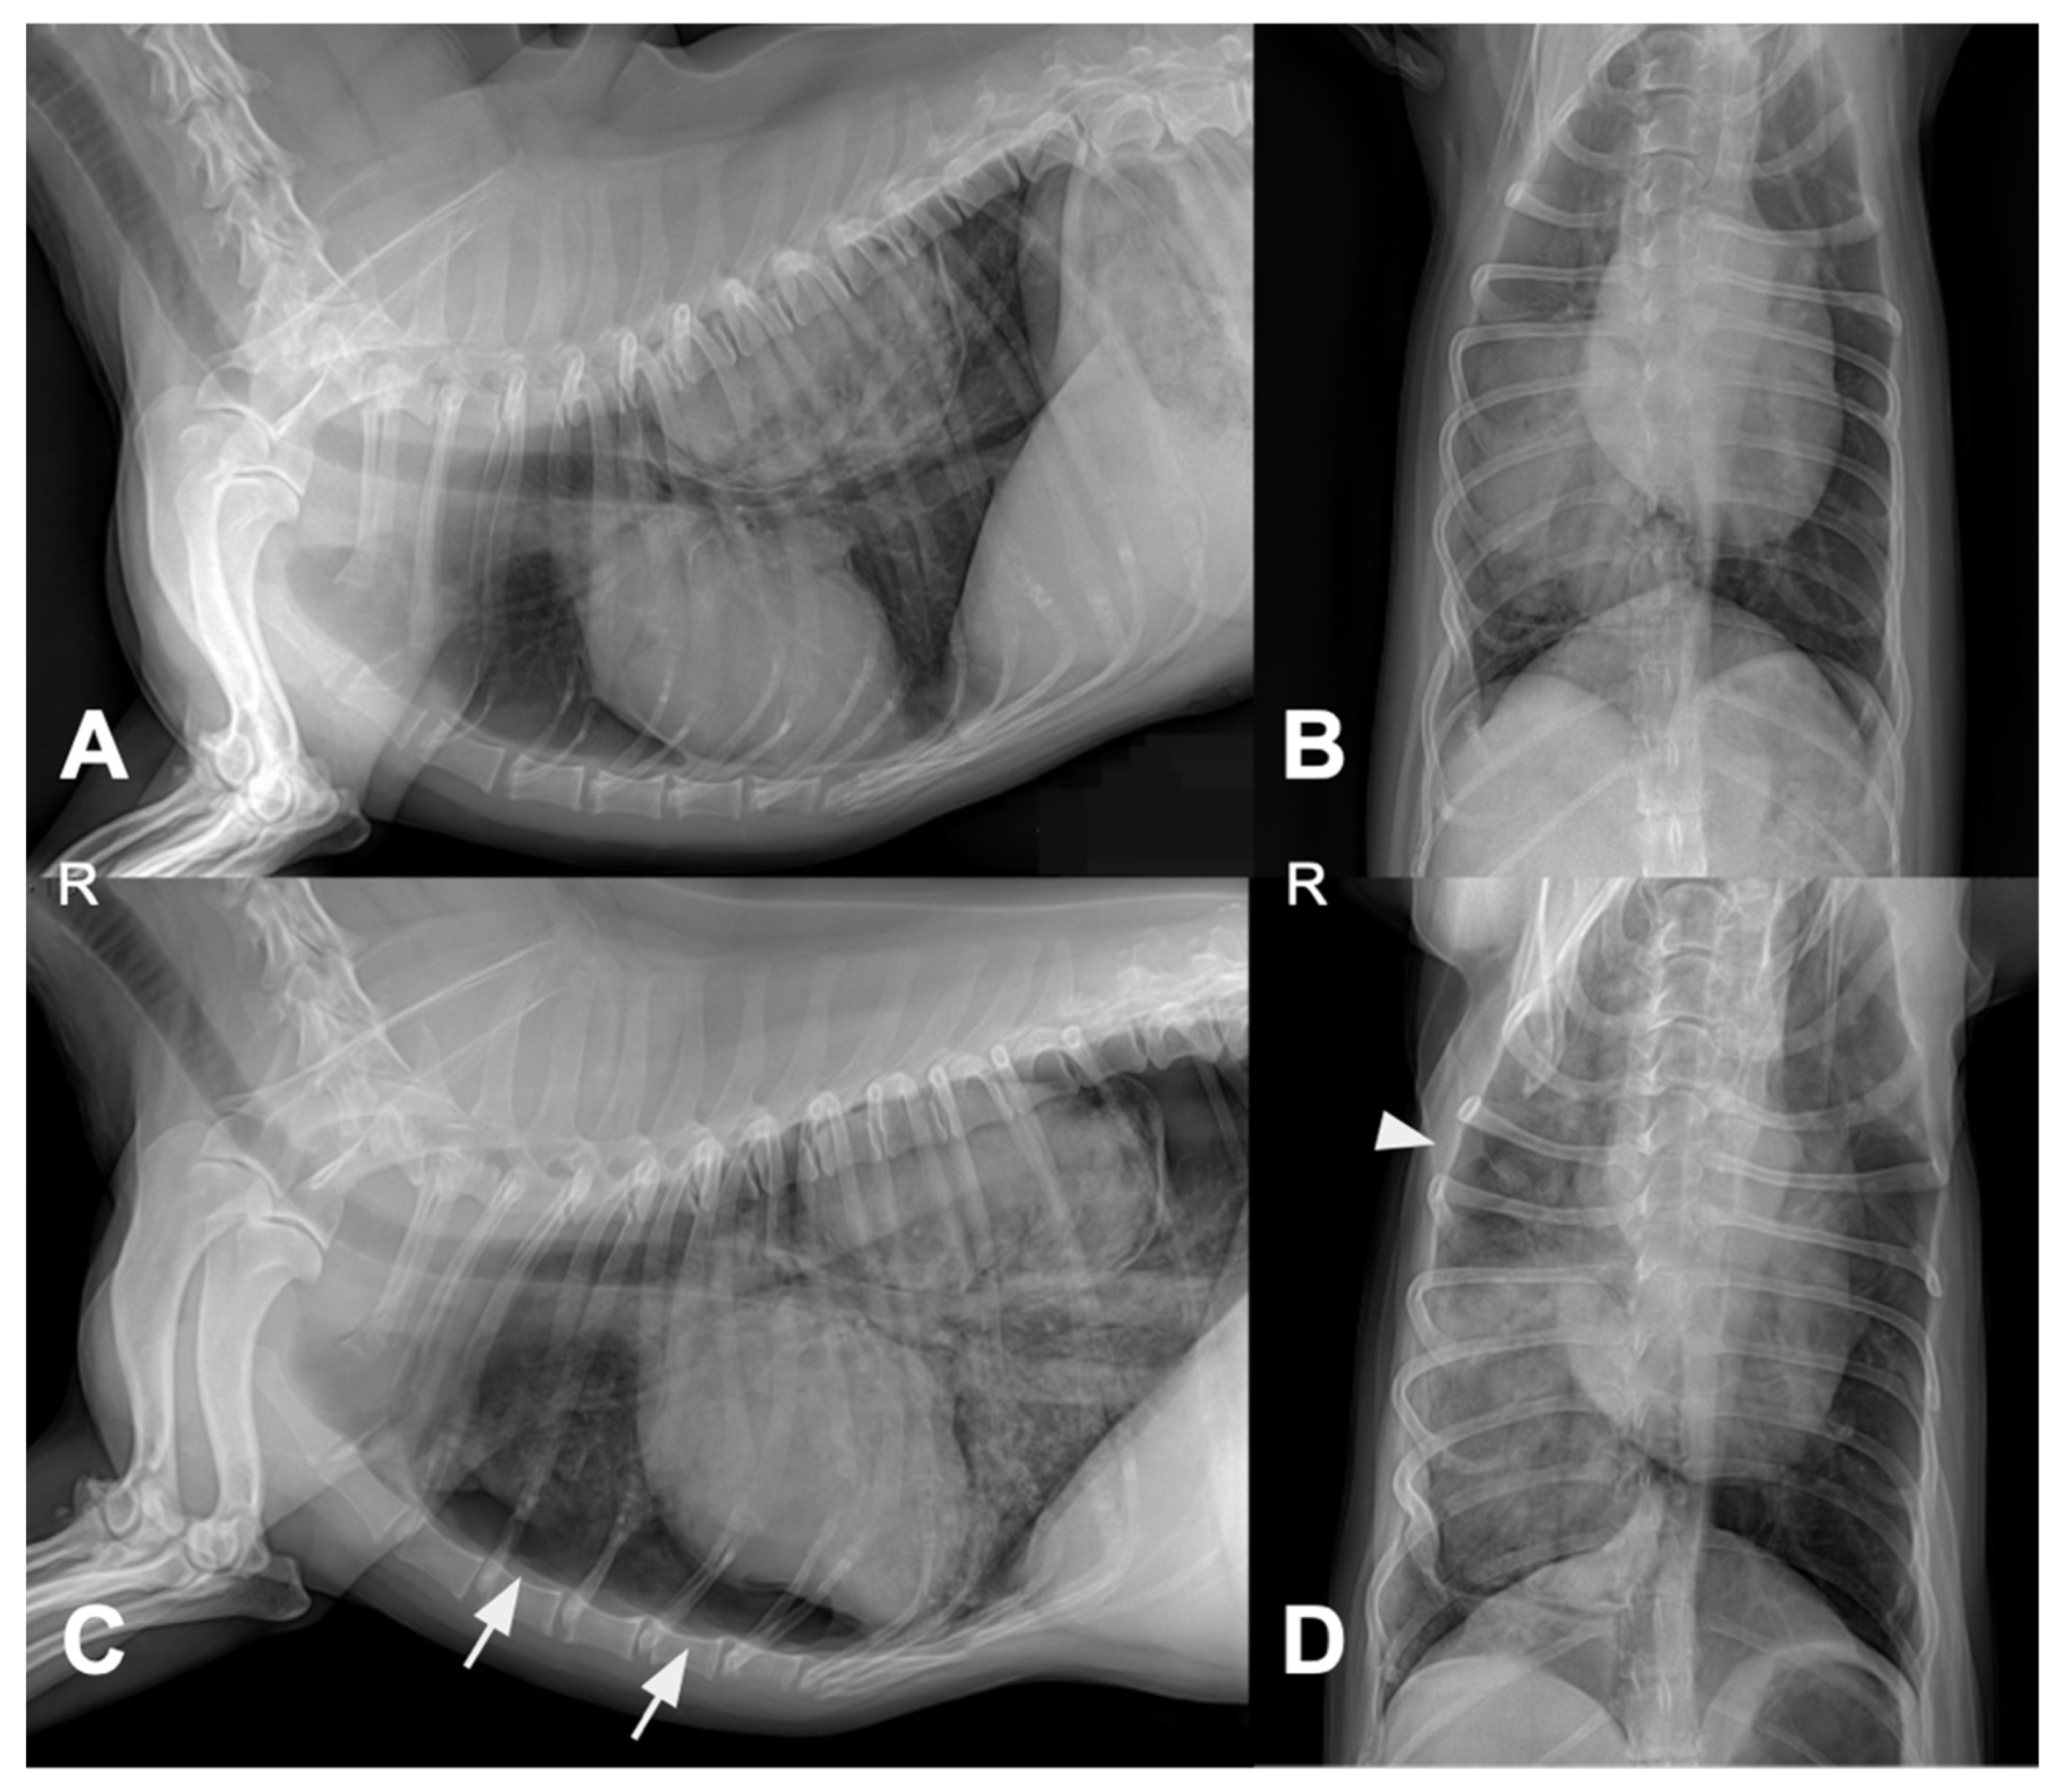

A 9-year and 8-month-old neutered male Welsh corgi weighing 13.5 kg was referred to our hospital after the incidental detection of pulmonary and splenic masses during routine health screening. At the time of presentation, the dog was clinically stable. However, the medical history included intermittent coughing, dyspnea, and cyanosis. Thoracic CT revealed an 81.3 mm pulmonary mass in the right caudal lung lobe extending into the accessory lobe. The middle tracheobronchial lymph node was enlarged and showed strong rim contrast enhancement, a CT feature commonly associated with metastatic lymph node involvement due to peripheral neoplastic infiltration and increased vascularization, making metastasis highly suspected (Figure 1). A 6.5 × 4.7 × 5.3 cm splenic mass was also identified.

Figure 1. Thoracic computed tomography (CT) images of the lung mass. (A) Transverse image showing a large soft-tissue attenuating mass (arrowhead) in the right caudal lung lobe (RCLL) with mild peritumoral emphysematous changes along the accessory lung lobe (ALL) dorsomedial margin. (B) Dorsal plane image showing the maximum diameter of the mass (arrowhead) measuring 81.3 mm. (C) Soft-tissue window image showing enlargement of the middle tracheobronchial lymph node (arrow) located caudal to the carina. Abbreviations: RCLL, right caudal lung lobe; ALL, accessory lung lobe; R, right side.